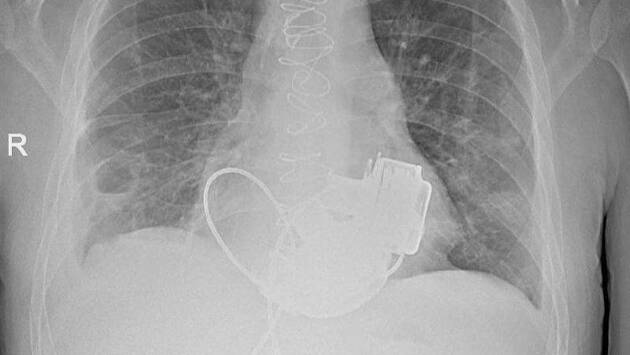

Уникальный пациент без пульса готовится к выписке из петербургской Мариинской больницы. Мужчине впервые в России имплантировали сразу два искусственных желудочка сердца. Об этом рассказали в официальном Telegram-канале городского комитета по здравоохранению.

В медицинское учреждение 36-летний мужчина поступил осенью 2025 года с кардиомиопатией и терминальной сердечной недостаточностью, показатели сердца говорили о том, что человек словно не жив, а уже мертв. Трансплантацию сердца пациенту делать было нельзя из-за некоторых осложнений.

В итоге главный врач больницы Игорь Реутский принял решение об имплантации не одного, а сразу двух искусственных желудочков сердца, потому что одного прибора было бы недостаточно.

«Операция продолжалась около четырех часов. Для наших специалистов самым сложным было синхронизировать работу двух искусственных желудочков сердца, но с этой задачей мы успешно справились. Это доказывает высокий уровень развития кардиохирургии в нашем городе», — рассказал главный внештатный специалист по сердечно-сосудистой хирургии Комитета по здравоохранению Санкт-Петербурга, академик РАН Геннадий Хубулава, под чьим руководством проводилась операция.

Несмотря на то, что послеоперационный период для пациента был непростым, он научился жить с приборами и надеется на скорую операцию трансплантации донорского сердца.